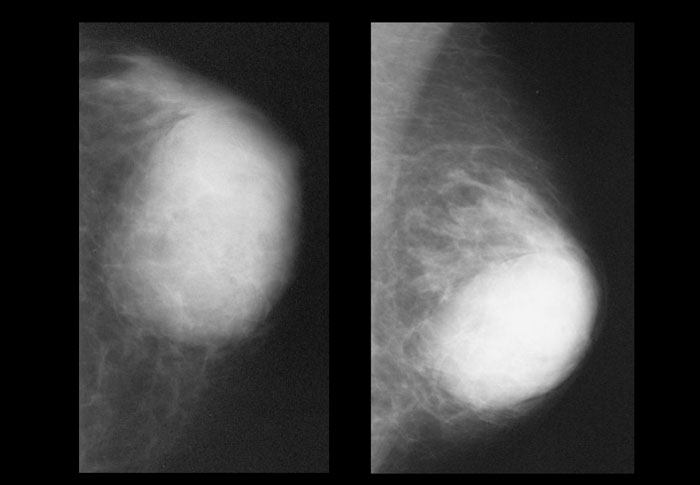

- Маммография. Рентгенологиялық әдістің бір түрі. Егде жастағы әйелдерге жиі қолданылады. Фиброзды өзгерістерді, ісік тәрізді түзілістерді көрсетеді. Ақпараттылығын арттыру үшін дуктографиямен толықтырылуы мүмкін. Нәтижелері күмәнді болса, цифрлық томосинтез жасалады. Кисталары бар науқастарға пневмокистография жүргізіледі.